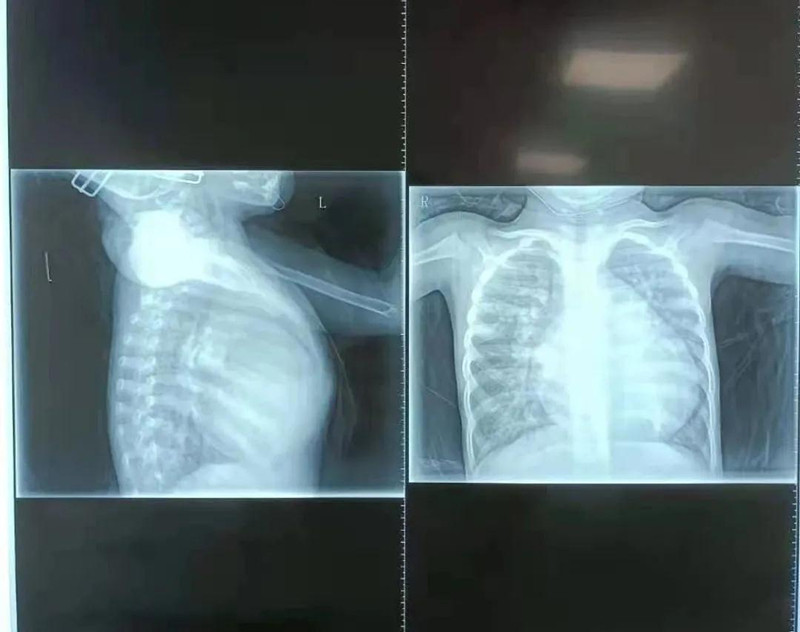

在啪啪网 小儿心脏病诊疗中心,杨明远医生初见馨馨印象极为深刻,4岁的孩子体重仅10.5公斤,由于心脏变大,她的胸骨被挤压得明显向前凸起。检查发现,馨馨心脏室间隔有直径17mm的缺损,导致左心室血液一部分流向右心室。同时,馨馨出生后动脉导管就未闭合,导致血液从主动脉分流到肺动脉。为了维持全身用血,左心室需要不断增加“劳动量”,而全身血液加上分流到右心室的血液最终都回到左心室,造成左心室严重增大,左室疏末径达到50.1mm,比正常成年人(正常成人左室疏末径为35-50mm)还要大。杨明远医生说,在先天性心脏病中,室间隔缺损比较常见,但像馨馨的心脏畸形严重到如此程度、对身体影响如此大的实属少见。